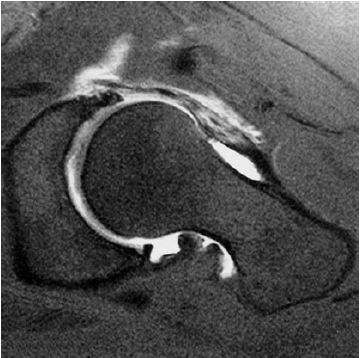

Axial Cut Magnetic Resonance Mr Arthrogram Of The Left Hip Download Scientific Diagram

Mr Arthrogram T2 Weighted Fat Suppressed Sequence Of A Right Hip In Download Scientific Diagram